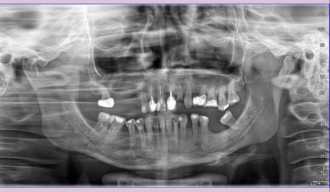

Wskazaniem po takiego leczenia są sytuacje, w których pojawiły się zmiany w okolicy wierzchołków korzeni lub podczas pierwszego leczenia kanałowego kanały zęba zostały opracowane i wypełnione w sposób nieprawidłowy – najczęściej nie zostały dopełnione do wierzchołka korzenia zęba. Obydwa przypadki można zdiagnozować na podstawie analizy obrazu radiologicznego.

Leczenie endodontyczne w Naszym Gabinecie odbywa się tylko i wyłącznie przy użyciu mikroskopu. Tylko odpowiednie powiększenie oraz doświadczenie lekarza pozwala na osiągnięcie odpowiedniego efektu ponownego leczenia kanałowego. Nasz specjalista Dr Mariusz Pietrzak wykonuje takie leczenie podczas jednego spotkania. Macie Państwo, zatem komfort nie tylko bezbolesnego leczenia, ponieważ zawsze odbywa się ono w znieczuleniu miejscowym, ale także kompleksowości ( na miejscu wykonujemy całą diagnostykę radiologiczną ) oraz sprawności leczenia, które można zakończyć podczas jednego spotkania.